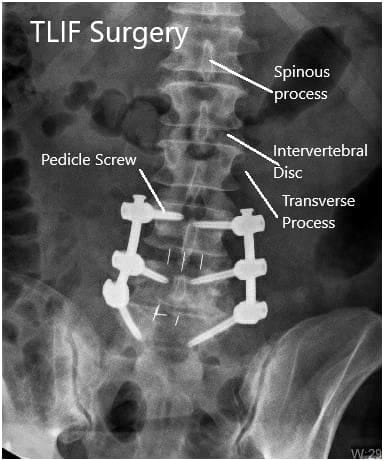

We first began with the left side and placed a size #60 mm length rod into position. We then secured it and ensured that there was an adequate amount of lumbar lordosis. We then also secured the right side rod with a similar length into position.

We then obtained final fluoroscopic images and were completely satisfied with our fixation and alignment. We then washed out the wounds with normal saline and vancomycin instilled into the wound. We proceeded to close the layers with a size #2 Vicryl sutures for the fascia layer followed by size #2-0 Vicryl suture for the subcutaneous skin and a running #4-0 Monocryl suture for the subcuticular layer.

Postoperative X-ray in AP and Lateral views.